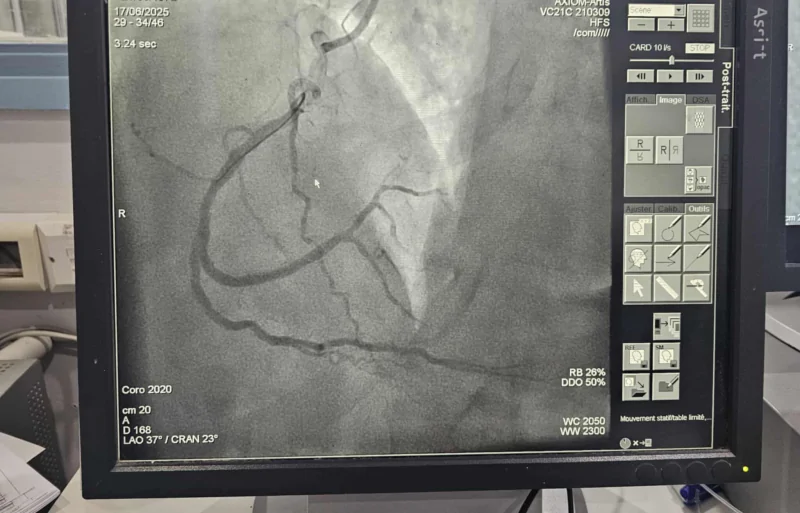

نجحت الفرق الطبية في مستشفيي الهادي شاكر والحبيب بورقيبة بصفاقس، بالتنسيق مع Samu 04، في إجراء 5 عمليات قسطرة قلبية في وقت قياسي لمرضى تعرّضوا لجلطات حادة، وذلك بفضل الاستخدام الفعّال لمنصة "نجدة TN".

وتتيح المنصة الرقمية تشخيص الحالة القلبية بشكل مبكّر وتوجيه المريض بسرعة نحو العلاج، مما يقلّص من نسب الوفاة والمضاعفات، وفق ما جاء على الصفحة الرسمية لوزارة الصحة.